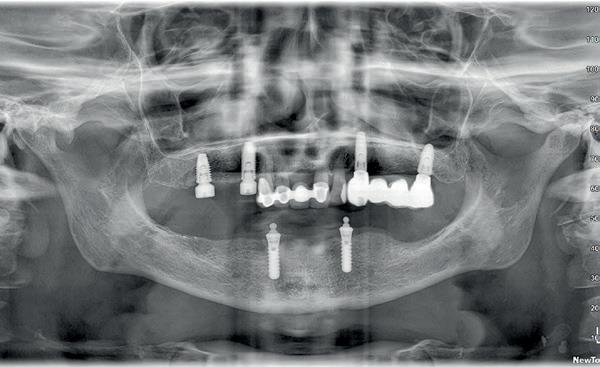

Tweede fase chirurgie

Na de genezingsperiode werd eerst een OPT röntgenopname vervaardigd om de genezing van de implantaten, kaakverbreding en sinusbodemelevatie te beoordelen. Er waren geen complicaties opgetreden. Bij de tweede fase chirurgie is het van absoluut belang dat er minimaal 2-3 mm gekeratiniseerd weefsel aan de buccale zijde van de implantaten wordt verkregen, anders kan de patiënt de implantaten niet goed reinigen en door de trekkrachten van de mucosa ontstaat al gauw peri-implantaire ontstekingen en recessies. De incisie hoeft niet van tuber tot tuber te zijn, maar 2 incisies van de 16 tot de 12 en 26 tot de 22 is voldoende, waarbij de incisie genoeg gekeratiniseerd weefsel aan de buccale zijde bevat, dat naar

hygiënist waarbij ook de mondhygiëne bij de brug wordt gecontroleerd. Op de OPT na 2 jaar (afbeelding 22) is het botniveau rondom de implantaten stabiel en is patiënt tevreden met zijn vaste brug.

22. Controle OPT na 2 jaar